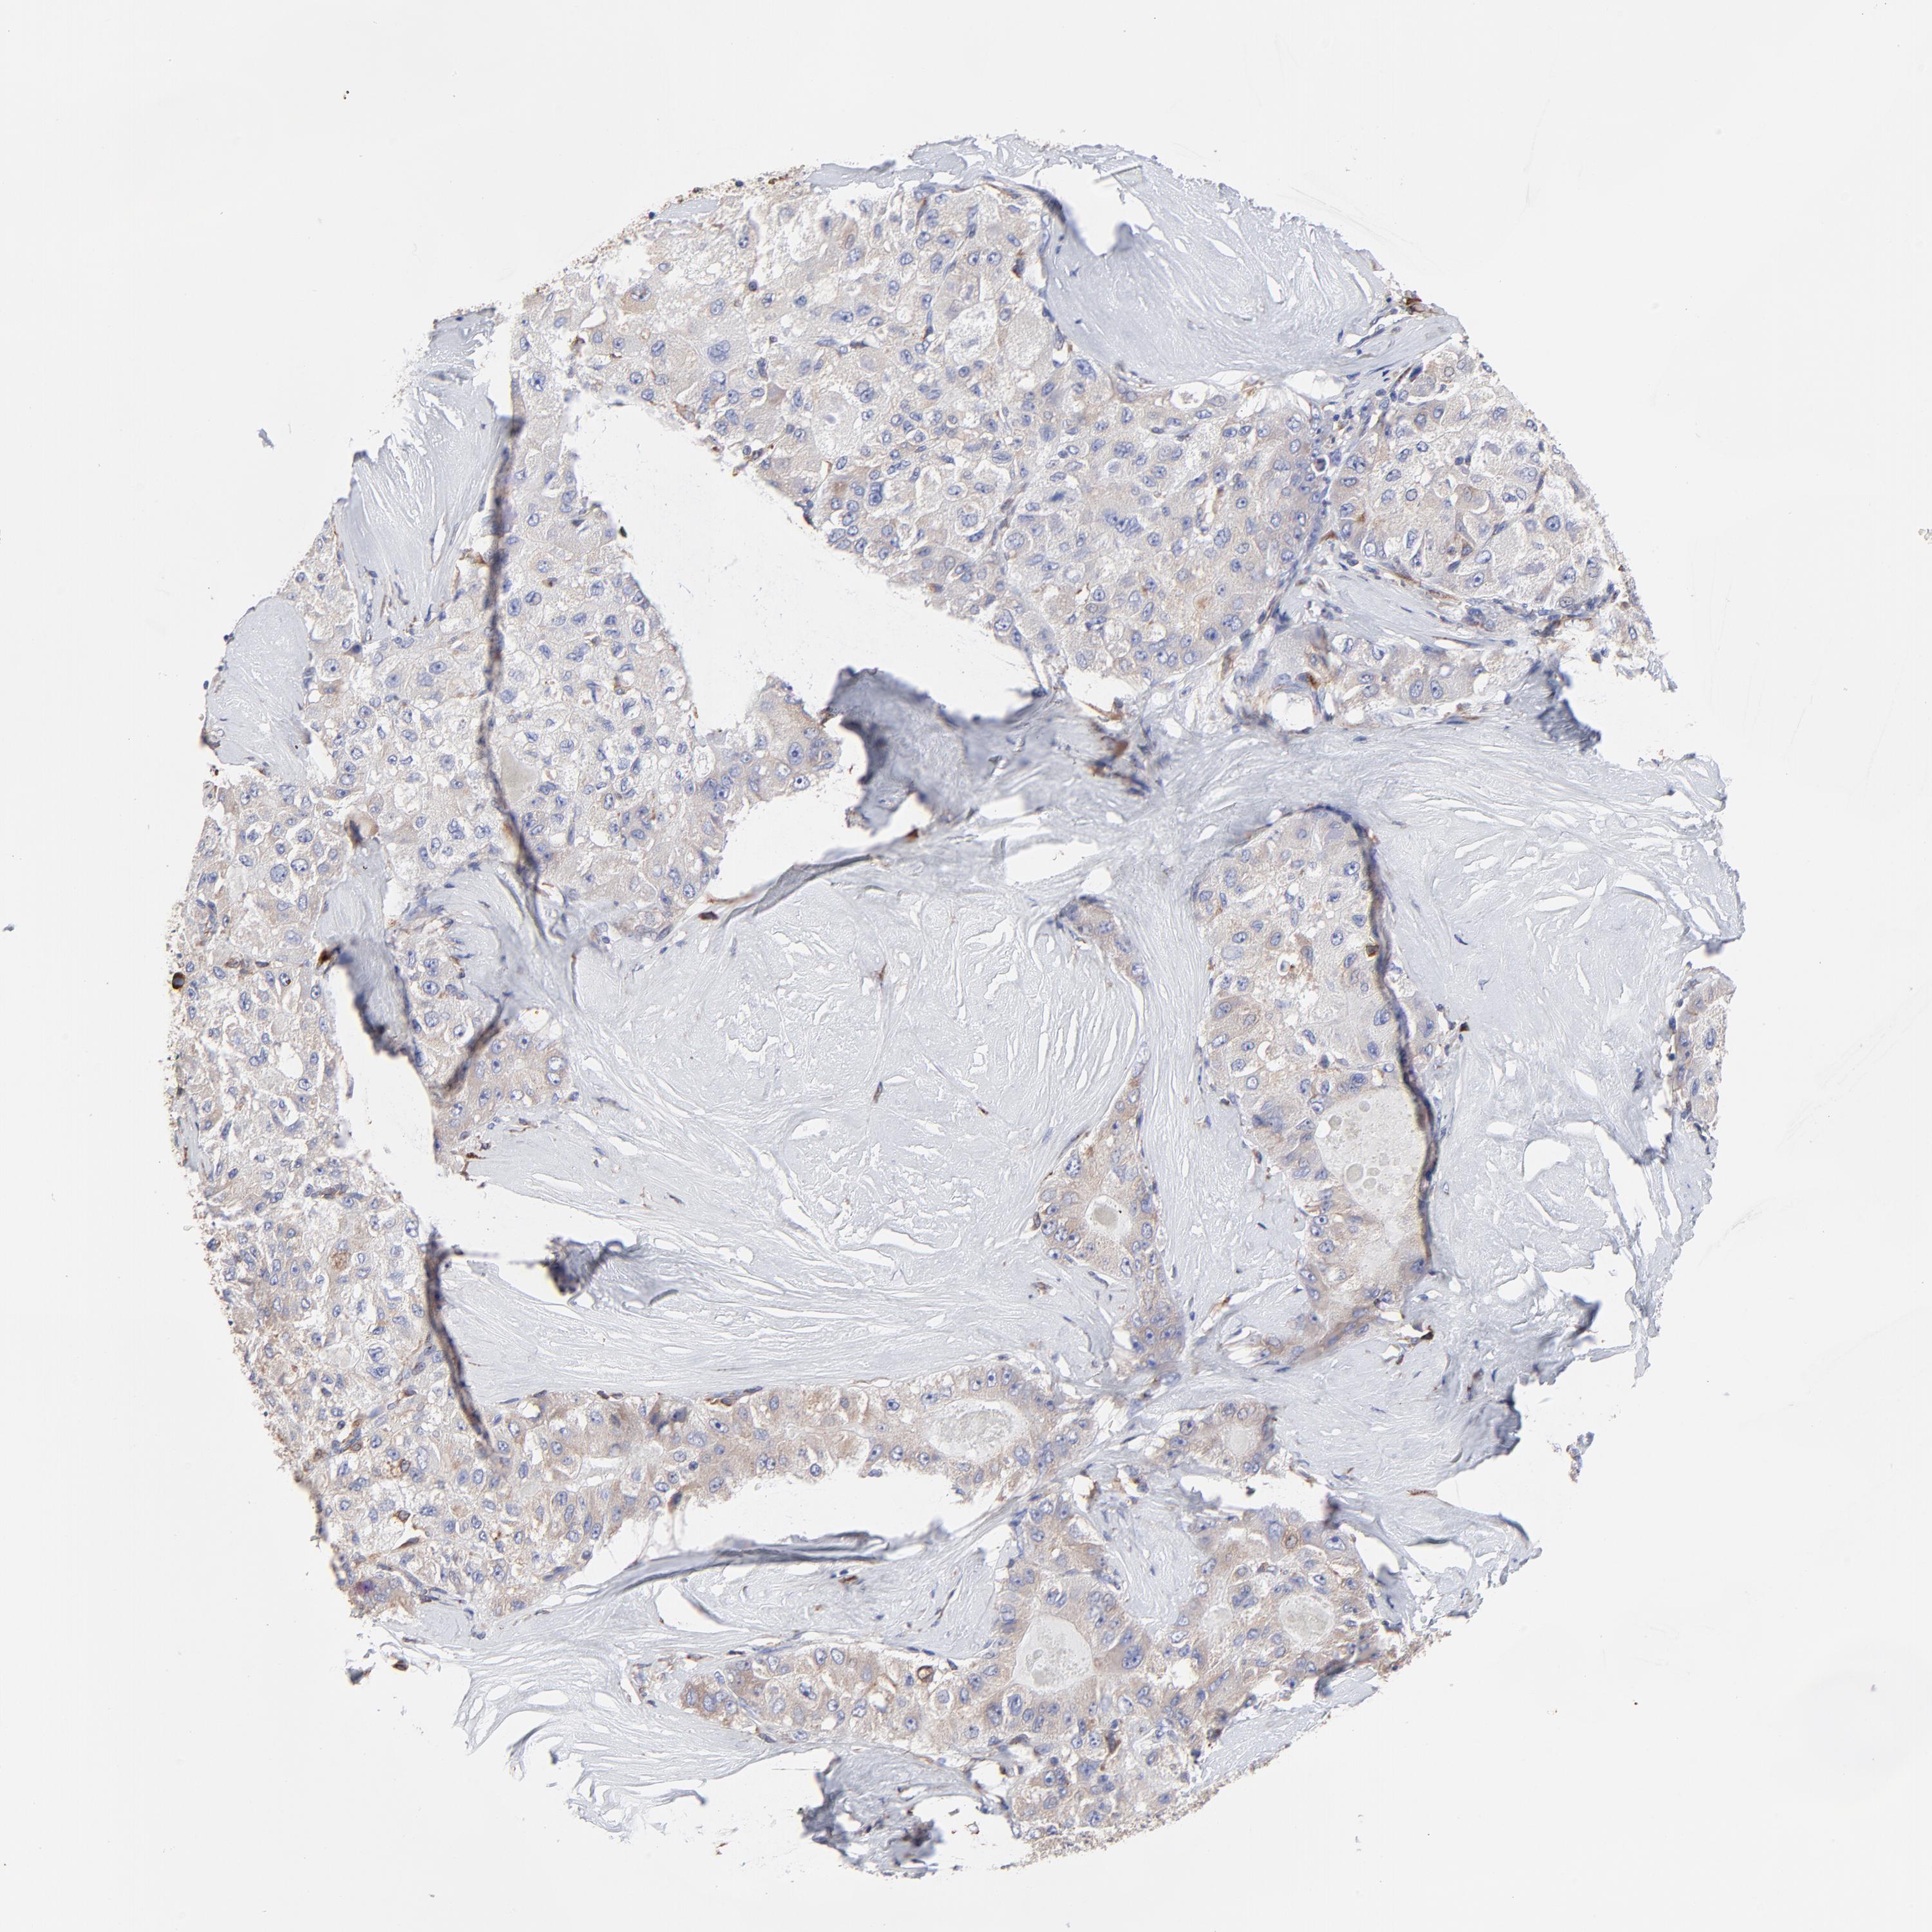

LIVER CANCER - Protein expressioni

A mouse-over function shows sample information and annotation data. Click on an image to view it in a full screen mode. Samples can be filtered based on level of antibody staining by selecting one or several of the following categories: high, medium, low and not detected. The assay and annotation is described here.

Note that samples used for immunohistochemistry by the Human Protein Atlas do not correspond to samples in the TCGA dataset.

Antibody stainingi

Antibody staining in the annotated cell types in the current human tissue is reported as not detected, low, medium, or high, based on conventional immunohistochemistry profiling in selected tissues. This score is based on the combination of the staining intensity and fraction of stained cells.

Each image is clickable and will lead to virtual microscopy that enables deeper exploration of all samples and also displays staining intensity scores, fraction scores and subcellular localization as well as patient and tissue information for each sample.

Antibody HPA002320

Antibody CAB037163

Staining

High

Medium

Low

Not detected

Intensity

Strong

Moderate

Weak

Negative

Quantity

>75%

75%-25%

<25%

None

Location

Nuclear

Cytoplasmic/membranous

Cytoplasmic/membranous,nuclear

Cholangiocarcinoma

Carcinoma, Hepatocellular, NOS